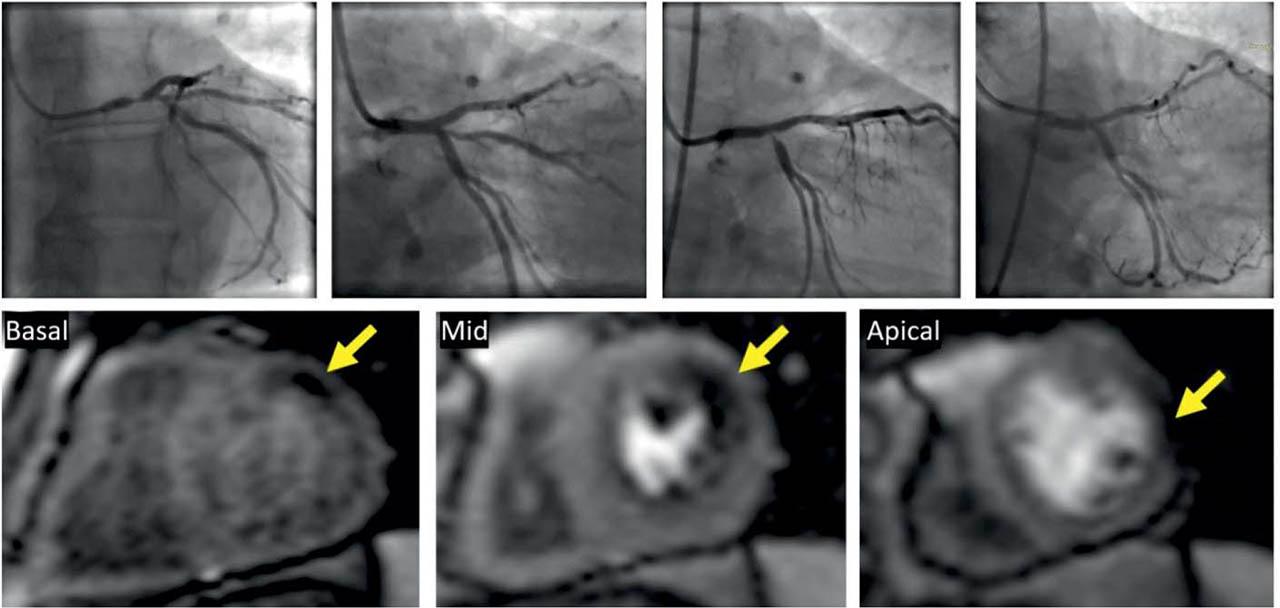

A positive stress test was noted in 21 patients (17.5%) (Figure 5). When the studies with inadequate vasodilator stress were excluded from the analysis the percentage of positive stress examinations increased to 18.58%. The majority of the positive stress patients were referred to CMR because they had a history of MI or previous revascularization or had intermediate lesion on ICA. Three of the patients without history of CAD had an abnormal CMR stress test (8.33%) (Table 3).

Figure 5

Stress perfusion CMR in a 70-year-old patient with a history of complex PCIs. His initial culprit lesion was a severe left main stenosis for which he was revascularized with a 2-stent technique. After one year, the stent on circumflex artery (Cx) had a severe ostial restenosis with chronic occlusion of the large ramus intermedius (RI). The Cx lesion was dilated with a DES but the RI could not be opened. Basal, mid and apical short axis slices acquired during maximal vasodilatory stress showing a perfusion defect in 3 myocardial segments: basal anterior, mid lateral and apical lateral wall respectively (yellow arrows). The topography of hypoperfused myocardium is compatible with the territory of the occluded intermediate ramus.